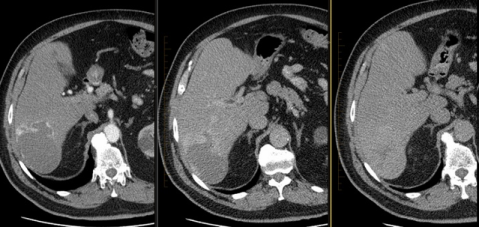

Hlavné diagnostické kritériá

Hlboká podkožná hmota

Hypoechogenic & hypervascularized tumor

Hlboká expanzia, viscerálne lézie

Liver Hemangioma – http://www.radpod.org/2011/08/04/liver-haemangioma/ | Restrepo R et al. Pediatr Radiol;41:895-904